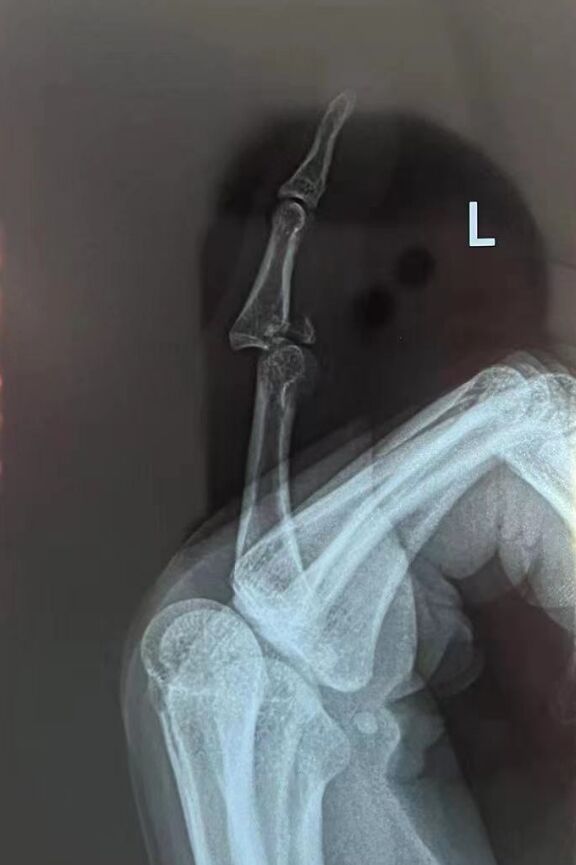

明天又来一个棘手的骨折脱位

还好这个是新鲜的

节前给做了

19岁学生